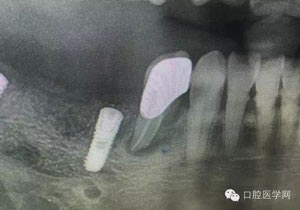

病例1:患者迫切希望保留自己的這一顆牙齒,根尖周陰影比較大,二度松動(dòng).而且旁邊有種植修復(fù)體,和患者溝通好后,治療好后觀察一個(gè)月后冠修復(fù),因?yàn)橛蟹N植的后期修復(fù),所以有了機(jī)會(huì)觀察,術(shù)后三個(gè)月和術(shù)后四個(gè)月,根尖恢復(fù)的還算不錯(cuò),希望能夠繼續(xù)觀察下去.這樣子的病例,做的時(shí)候我們一定要非常的小心,和患者要有充分的溝通以及不同科室的溝通然后決定怎么樣做比較好,假如就是出現(xiàn)了問(wèn)題,到時(shí)候我們也比較好處理些,免得我們自己到時(shí)候不好收?qǐng)觥?/span>